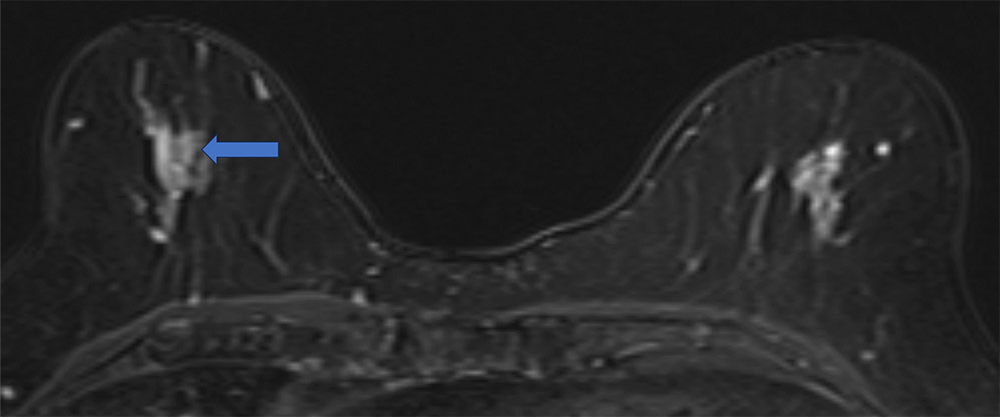

4. ダイナミックMRI 造影前 早期相 遅延相

病変は扁平な形状で均一に増強される。ダイナミックMRIの増強パターンはfast and plateauであった。

ダイナミックMRI 早期相

ダイナミックMRI 遅延相

5. Ultrafast DCE (20相目、造影剤投与開始から58秒後)

病変は周囲乳腺実質よりやや強く増強されている。